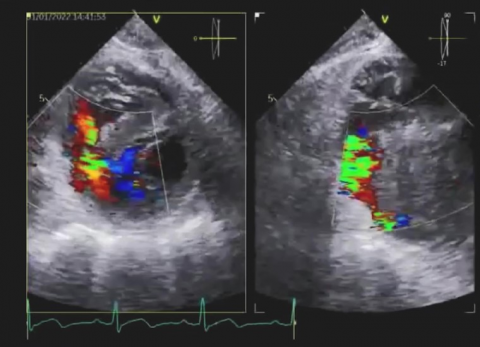

Wideo Echokardiografia. Przypadek 32

dr hab. n. med. prof. UJ Andrzej GackowskiPacjentka z dusznością spoczynkową, po wymianie zastawki mitralnej.